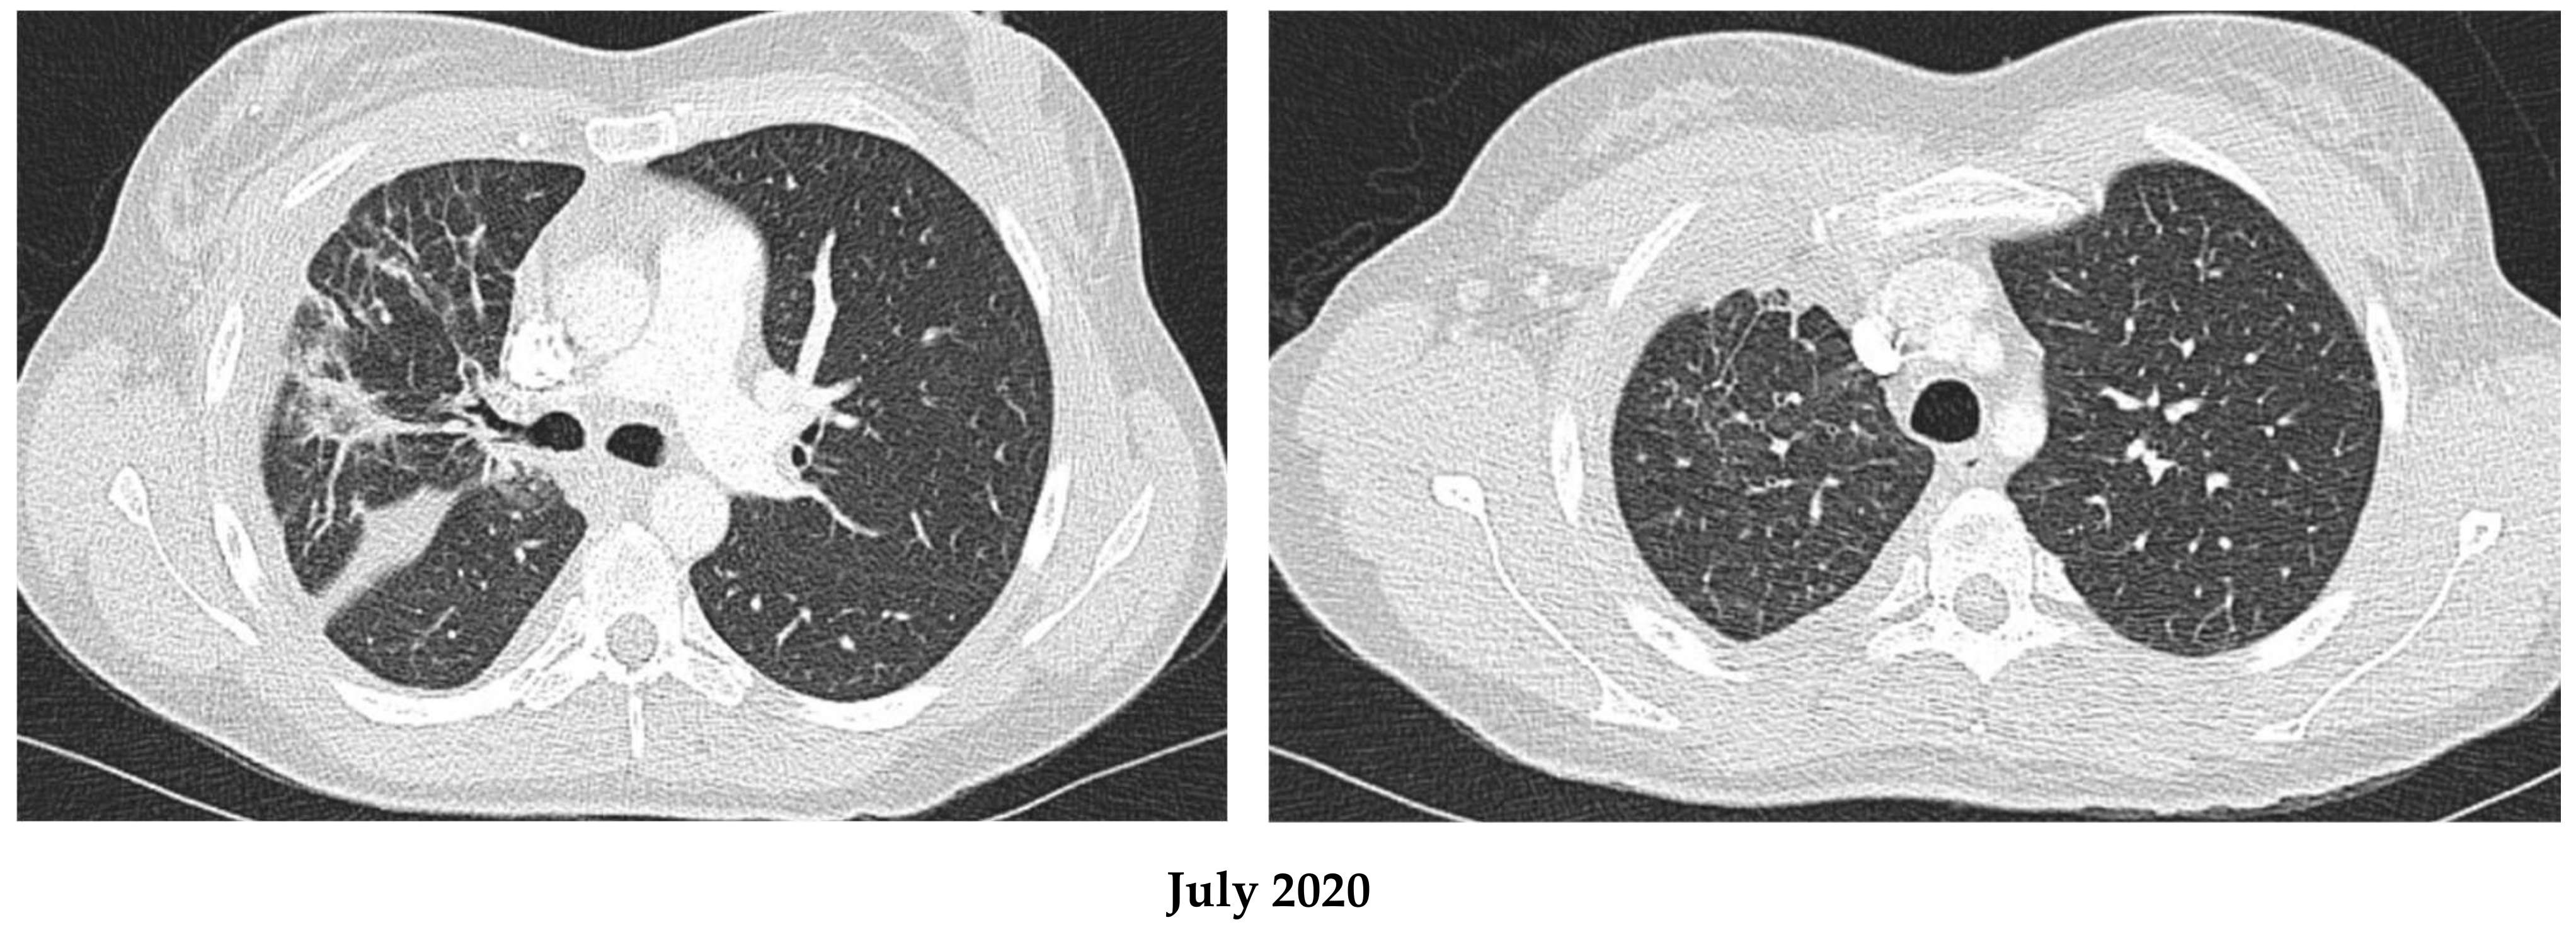

2.1. Patient 1